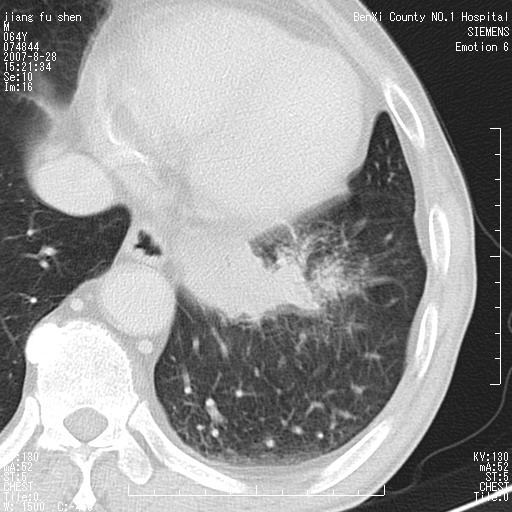

男、64、咳嗽、发烧一周、左肺呼吸音稍弱。既往肺结核,右手结核。

本次扫描患者未带原片,左肺下叶发现病灶。左肺上叶空洞,5组淋巴结肿大,1cm左右。

左肺下叶前内基底段支气管明显偏心性狭窄,周围分叶状肿块,伴有阻塞性肺炎,支持肺癌可能性大。

考虑左肺中央型肺癌并阻塞性肺炎

考虑左肺中央型肺癌并阻塞性肺炎,建议纤支镜检查